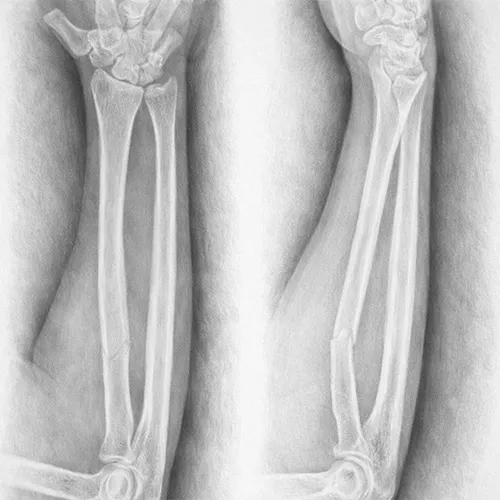

Intervenții chirurgicale de artroplastii de șold/genunchi, osteosinteze complexe, artroscopii. Raportare cazuri, plan terapeutic, documente de externare. Consultații în ambulatoriu, diagnostic și stabilirea conduitei terapeutice.

Evaluare clinică, diagnostic și plan terapeutic. Participare la intervenții chirurgicale, sinteză osoasă, artroscopii și artoplastii. Gărzi, evaluare urgențe ortopedice în UPU. Management traumatologie complexă.